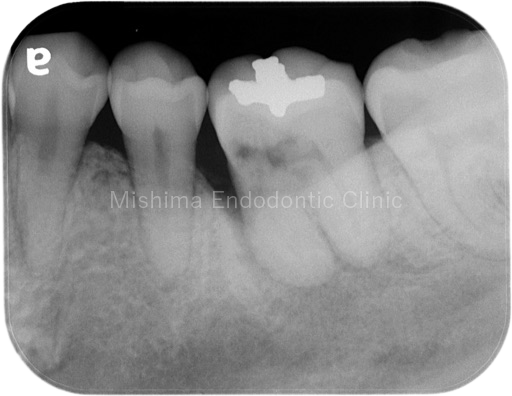

Before

| 治療内容 | 矯正治療の既往あり。CBCTから侵襲性歯頚部吸収、歯髄診査により歯髄壊死と診断。垂直性骨欠損の改善と吸収部の封鎖を補綴で行うべく、根管治療後にアップライトを行った。術前には7mmのポケットを認めたが、術後は全周ポケット2mmで歯槽骨頂の水平性が獲得でき、経過は良好。 |